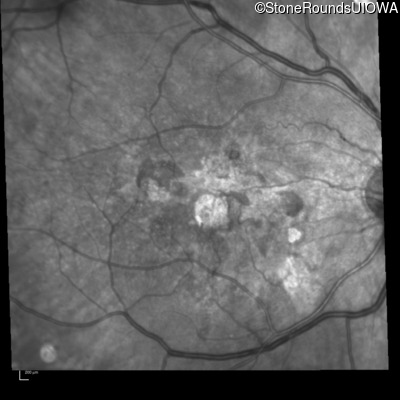

Infrared Fundus Photograph - Right - 20/80 -1

Exemplar